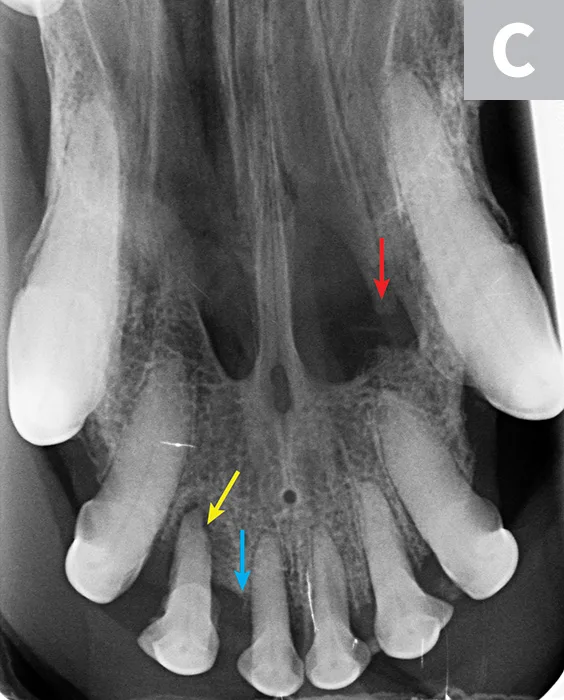

Figure 2

Dental radiographs of the right (A) and left (B) maxillary canine teeth (lateral views) and the rostral maxillae (C; occlusal view) confirmed mild horizontal and severe vertical bone loss at the mesial aspect of both maxillary canine teeth. Moderate to severe horizontal bone loss at the right maxillary first incisor tooth (blue arrow) and total loss of attachment with inflammatory root resorption at the right maxillary second incisor tooth (yellow arrow) were present. The remaining maxillary incisor teeth were affected by mild horizontal bone loss. Although the occlusal view of the rostral maxillae is slightly asymmetric, osteolysis was evident in the area of the left palatine fissure (red arrow). Mild horizontal bone loss was diagnosed at several other teeth. In addition, retained root tip of the left maxillary (presumably) first premolar tooth (white arrow) was identified.